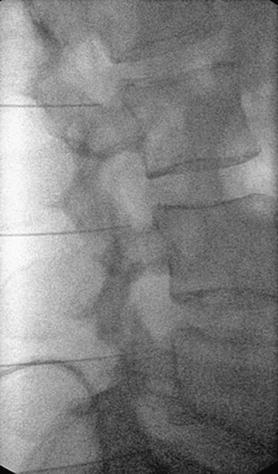

Στην ουραία επισκληρίδιο έγχυση υπό ακτινοσκοπική καθοδήγηση, εισάγεται ένας καθετήρας μέσω του ιερού τρήματος και προωθείται έως το επίπεδο στης κατώτερης οσφυϊκής μοίρας, όπου γίνεται η έγχυση διαλύματος τοπικού αναισθητικού και στεροειδούς.

Στην διατρηματική έγχυση, υπό ακτινοσκοπική καθοδήγηση, το φαρμακευτικό διάλυμα χορηγείται απευθείας στο σημείο εξόδου της νευρικής ρίζας, για την αντιμετώπιση του ριζιτικού άλγους.